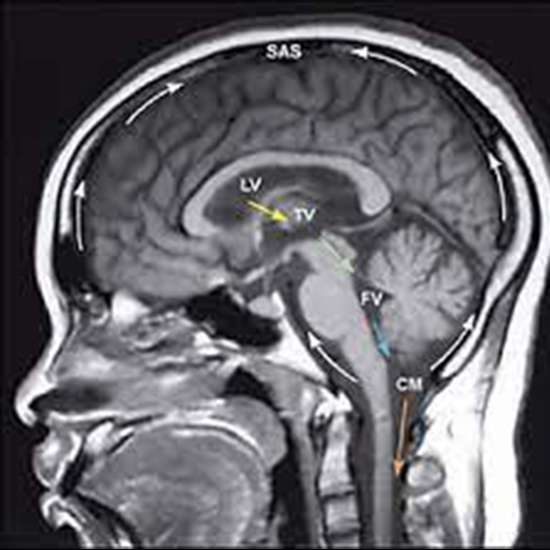

A head MRI is a medical imaging method that uses radio waves and a high magnetic field to produce exact images of the brain, skull, and surrounding tissues.

A head MRI is a medical imaging method that uses radio waves and a high magnetic field to produce exact images of the brain, skull, and surrounding tissues. Medical experts can get high-resolution images of the brain to help with the identification of a wide range of illnesses, including tumours, haemorrhages, strokes, inflammation, infections, and other irregularities.